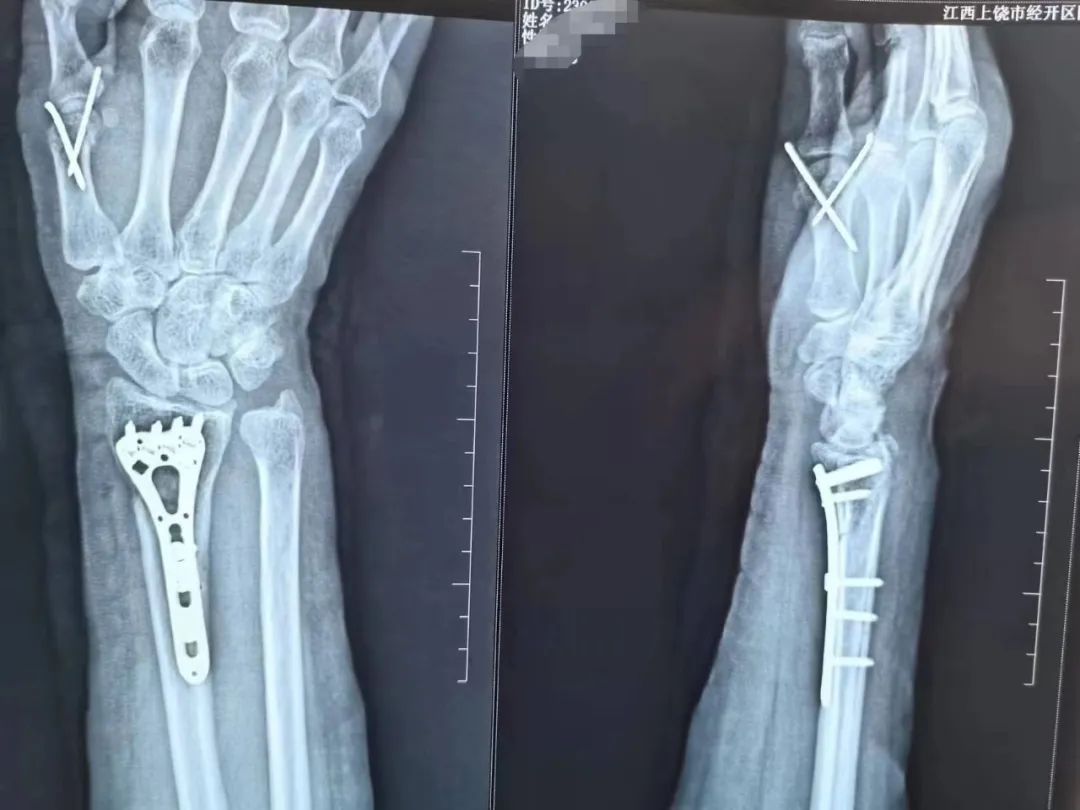

累及关节面的粉碎性骨折、开放性骨折、保守治疗效果欠佳者就需要进行手术治疗。就是通过做手术在直视下把骨头断的地方对好,然后用钢板、螺钉或者克氏针固定住,维持骨断端稳定不移位,待骨断端长在一起就痊愈了。

这种直视下复位的方法,骨折复位程度更好,很多累及关节的桡骨远端骨折患者,强求保守治疗,手法复位很难完全恢复关节面的平整,关节面最后如同不平整的地面一样愈合后,活动的时候容易磕磕碰碰,关节就容易痛,导致创伤性关节炎。并且通过内固定物直接固定骨断端的方式,也不容易再次移位,术后可以在医师指导下早期行腕关节康复锻炼,从而较大程度的恢复腕关节功能。